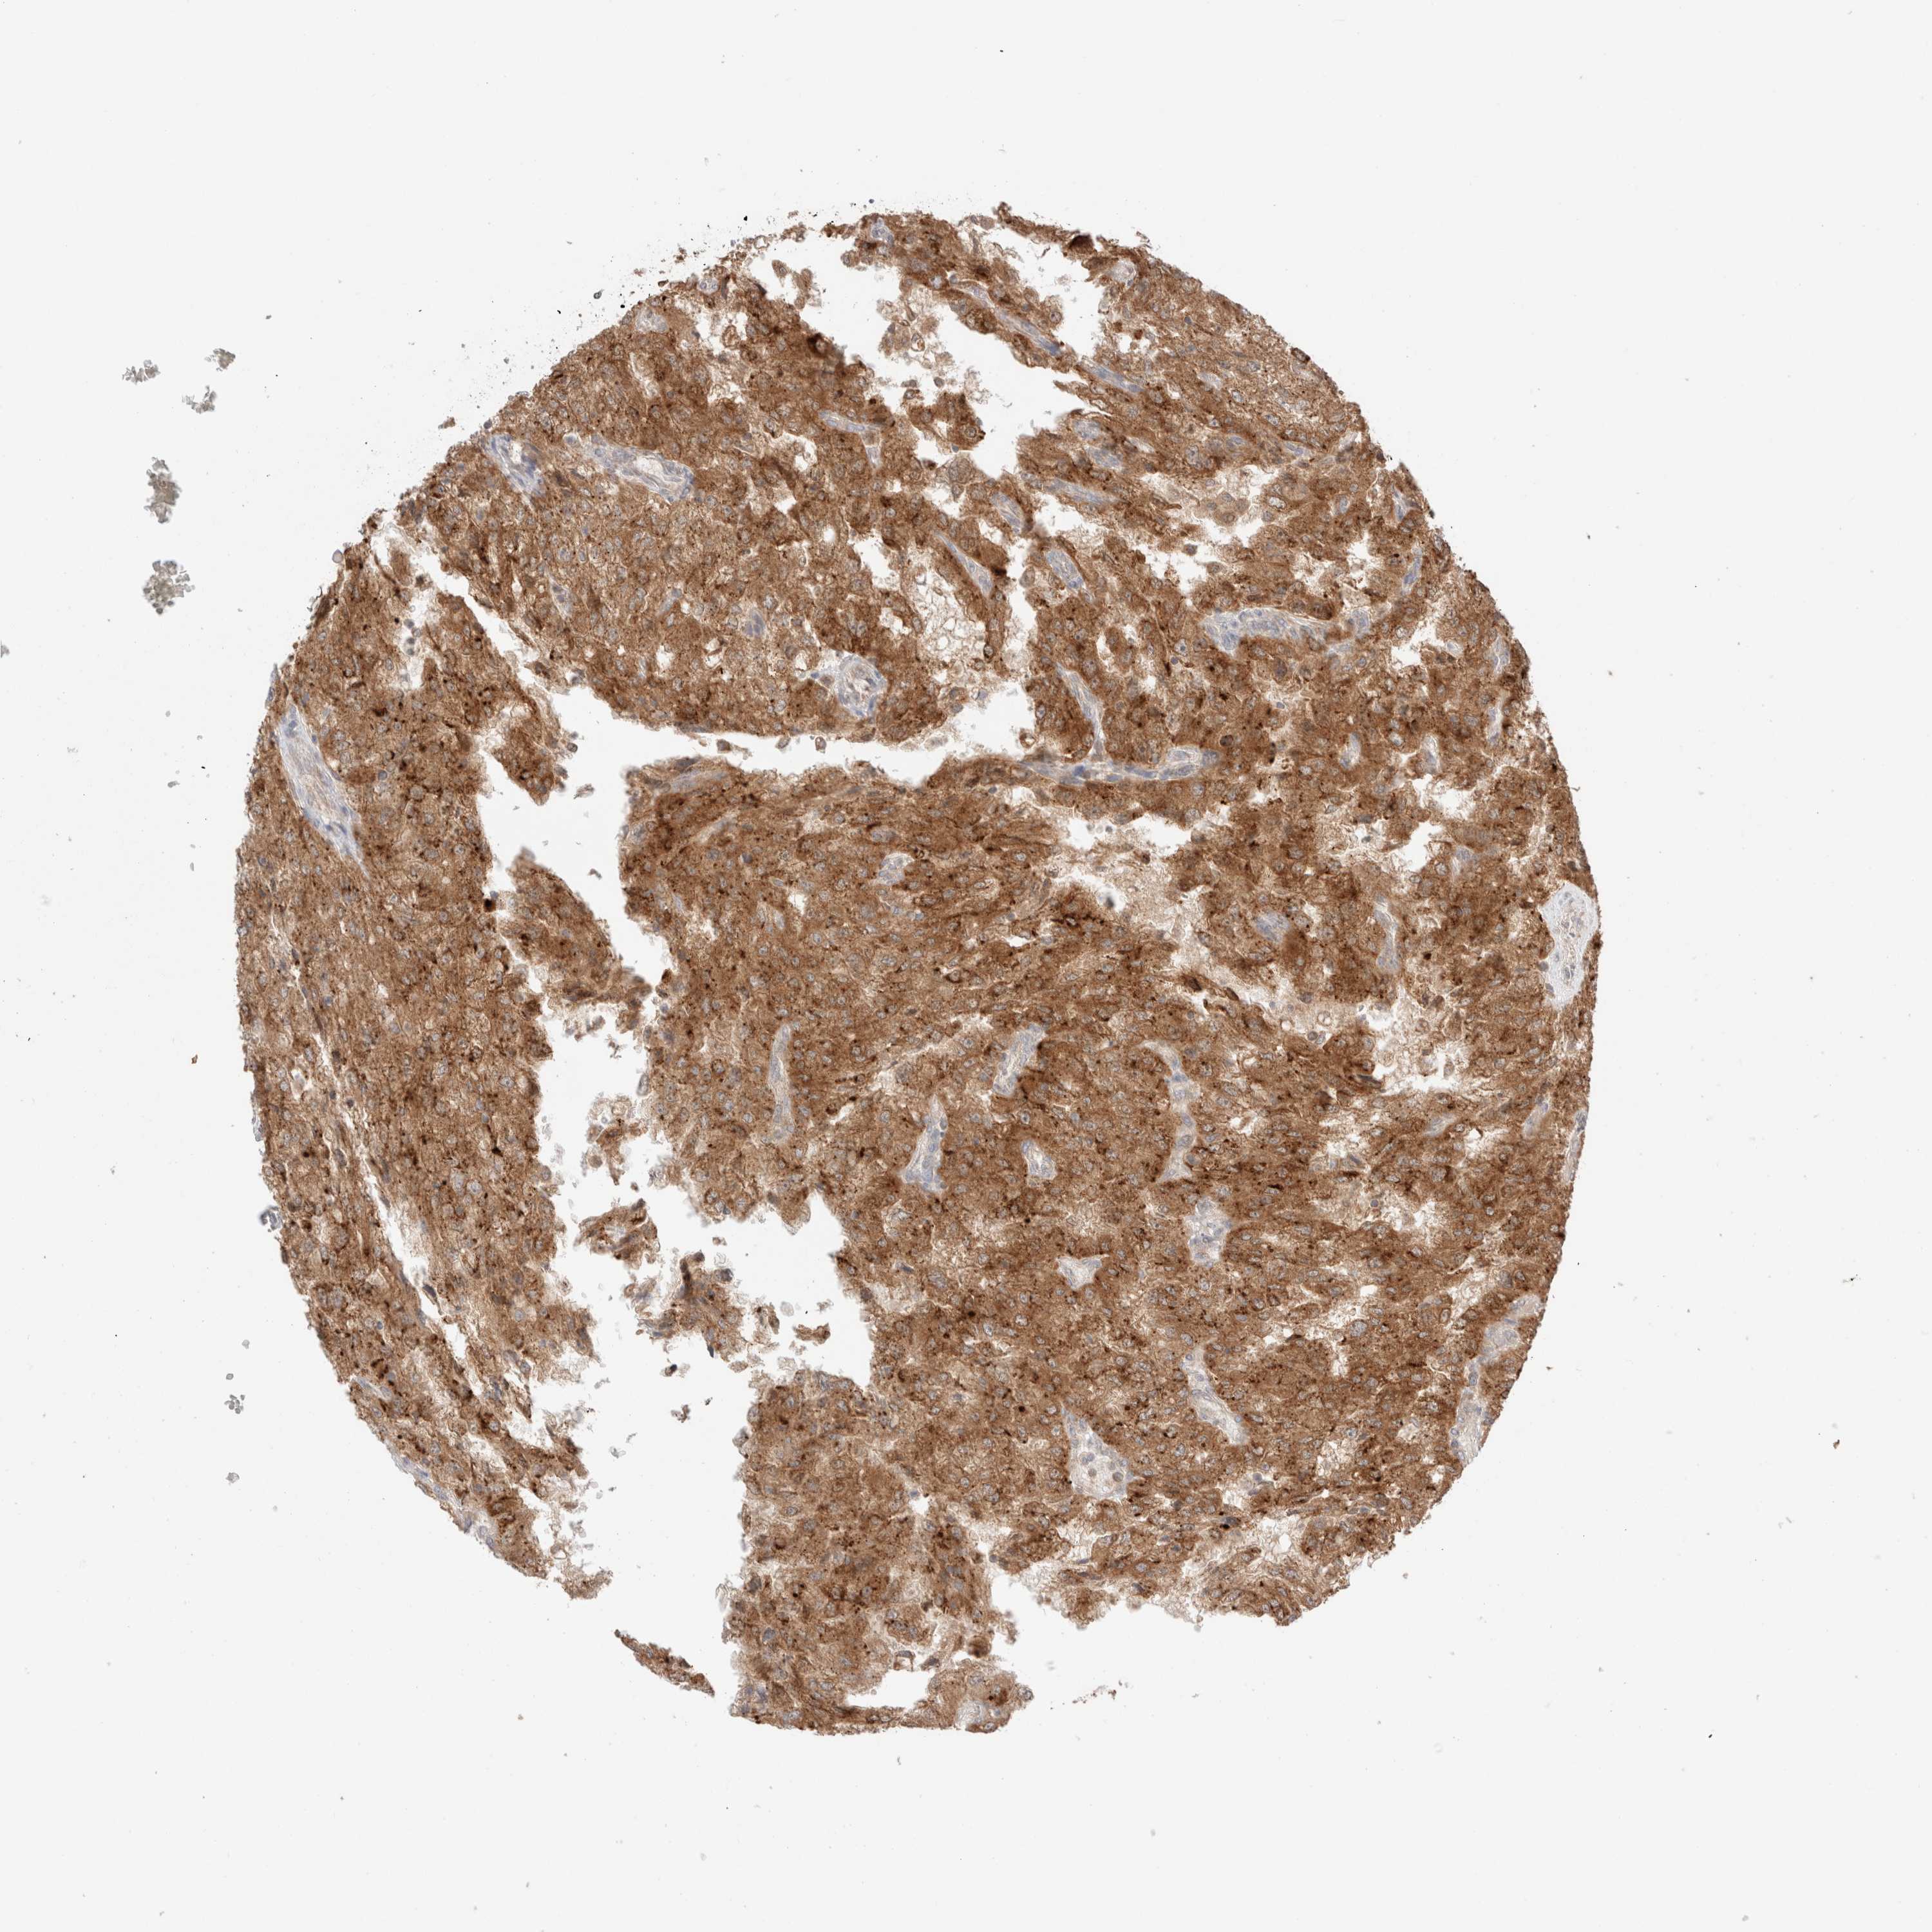

KIDNEY RENAL CLEAR CELL CARCINOMA (VALIDATION) - Interactive survival scatter ploti

The Survival Scatter plot shows the clinical status (i.e. dead or alive) for all individuals in the patient cohort, based on the same data that underlies the corresponding Kaplan-Meier plots. Patients that are alive at last time for follow-up are shown in blue and patients who have died during the study are shown in red.

The x-axis shows the expression levels (FPKM) of the investigated gene in the tumor tissue at the time of diagnosis. The y-axis shows the follow-up time after diagnosis (years). Both axes are complimented with kernel density curves demonstrating the data density over the axes. The top density plot shows the expression levels (FPKM) distribution among dead (red) and alive patients (blue). The right density plot shows the data density of the survived years of dead patients with high and low expression levels respectively, stratified using the cutoff indicated by the vertical dashed line through the Survival Scatter plot. This cutoff is automatically defined based on the FPKM cutoff that minimizes the p-score. The cutoff can be changed by dragging the vertical line or by entering a cutoff value in the square labeled "Current cut-off".

Under the Survival Scatter plot the p-score landscape (black curve; left axis) is shown together with dead median separation (red curve; right axis). Dead median separation is the difference in median mRNA expression between patients who have died with high and low expression, respectively. It is calculated as follows: median FPKM expression of dead patients with high expression - median FPKM expression of dead patients with low expression. This is intended to aid the user in visually exploring custom cutoffs and the associated p-scores and dead median separation.

Individual patient data is displayed and can be filtered by clicking on one or more of the category buttons on the top of the page. Categories describing expression level and patient information include: high, low, alive, dead, female, male and tumor stages. The scale of the x-axis can be toggled between linear and log-scale by clicking on the "x log" button. Mouse-over function shows TCGA ID, patient information and mRNA expression (FPKM) for each patient.

& Survival analysisi

Kaplan-Meier plots summarize results from analysis of correlation between mRNA expression level and patient survival. Patients were divided based on level of expression into one of the two groups "low" (under cut off) or "high" (over cut off). X-axis shows time for survival (years) and y-axis shows the probability of survival, where 1.0 corresponds to 100 percent.

XKR4 is not prognostic in Kidney Renal Clear Cell Carcinoma (validation)

TCGA RNA samplesi

RNA-seq data is reported as average FPKM (number Fragments Per Kilobase of exon per Million reads), generated by the The Cancer Genome Atlas (TCGA) .

Normal distribution across the dataset is visualized with box plots, shown as median and 25th and 75th percentiles. Points are displayed as outliers if they are above or below 1.5 times the interquartile range. FPKM values of the individual samples are presented next to the box plot.

Average pTPM 0.0

Number of samples 100